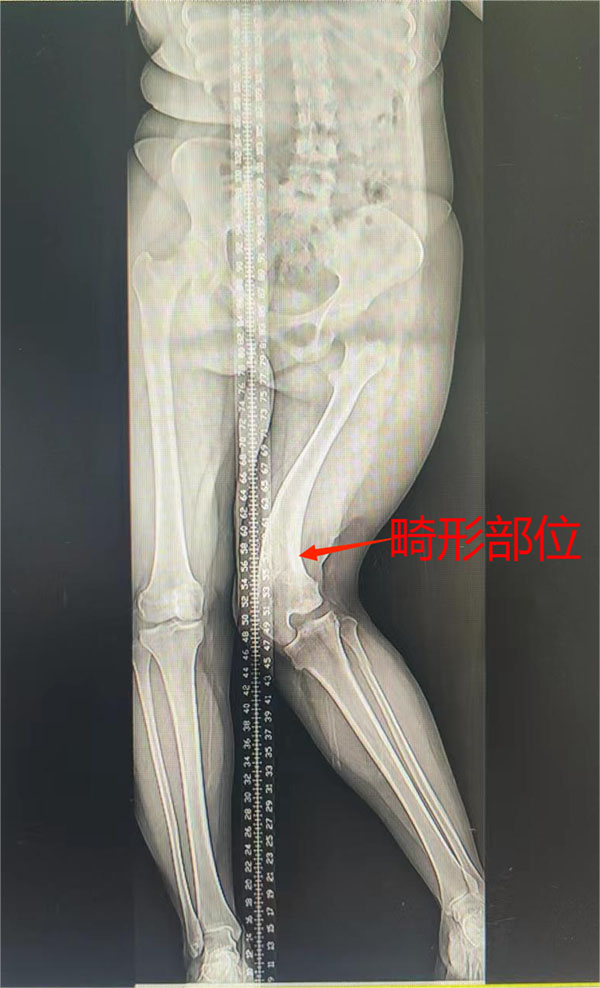

玉林市中西医结合骨科矫形骨科治疗过一位特殊的老病号—封小妹。该患者年仅20岁,但已经多次和医院打交道。不过与以往不同的是,这次患者是面带笑容来住院的,因为困扰多年的“剪刀腿”问题,终于要彻底解决了。

时间回溯到2005年,那时候封小妹才5岁,因玩耍不小心跌倒,摔断了左大腿骨,在当地医院行手术治疗。因受伤时损伤了股骨远端的骨骺线(生长发育线),术后不幸出现了严重的后遗症,骨折端畸形愈合,左大腿逐渐出现弯曲畸形。此后多年间,封小妹的家人带着她到全国各地多家医院求医,当时的接诊医师了解病情后,都直摇头,纷纷表示这么严重的畸形就算治疗,效果也不好。一次又一次的失望,封小妹和她的家人们逐渐产生放弃治疗的念头。

患者术前外观图和DR片